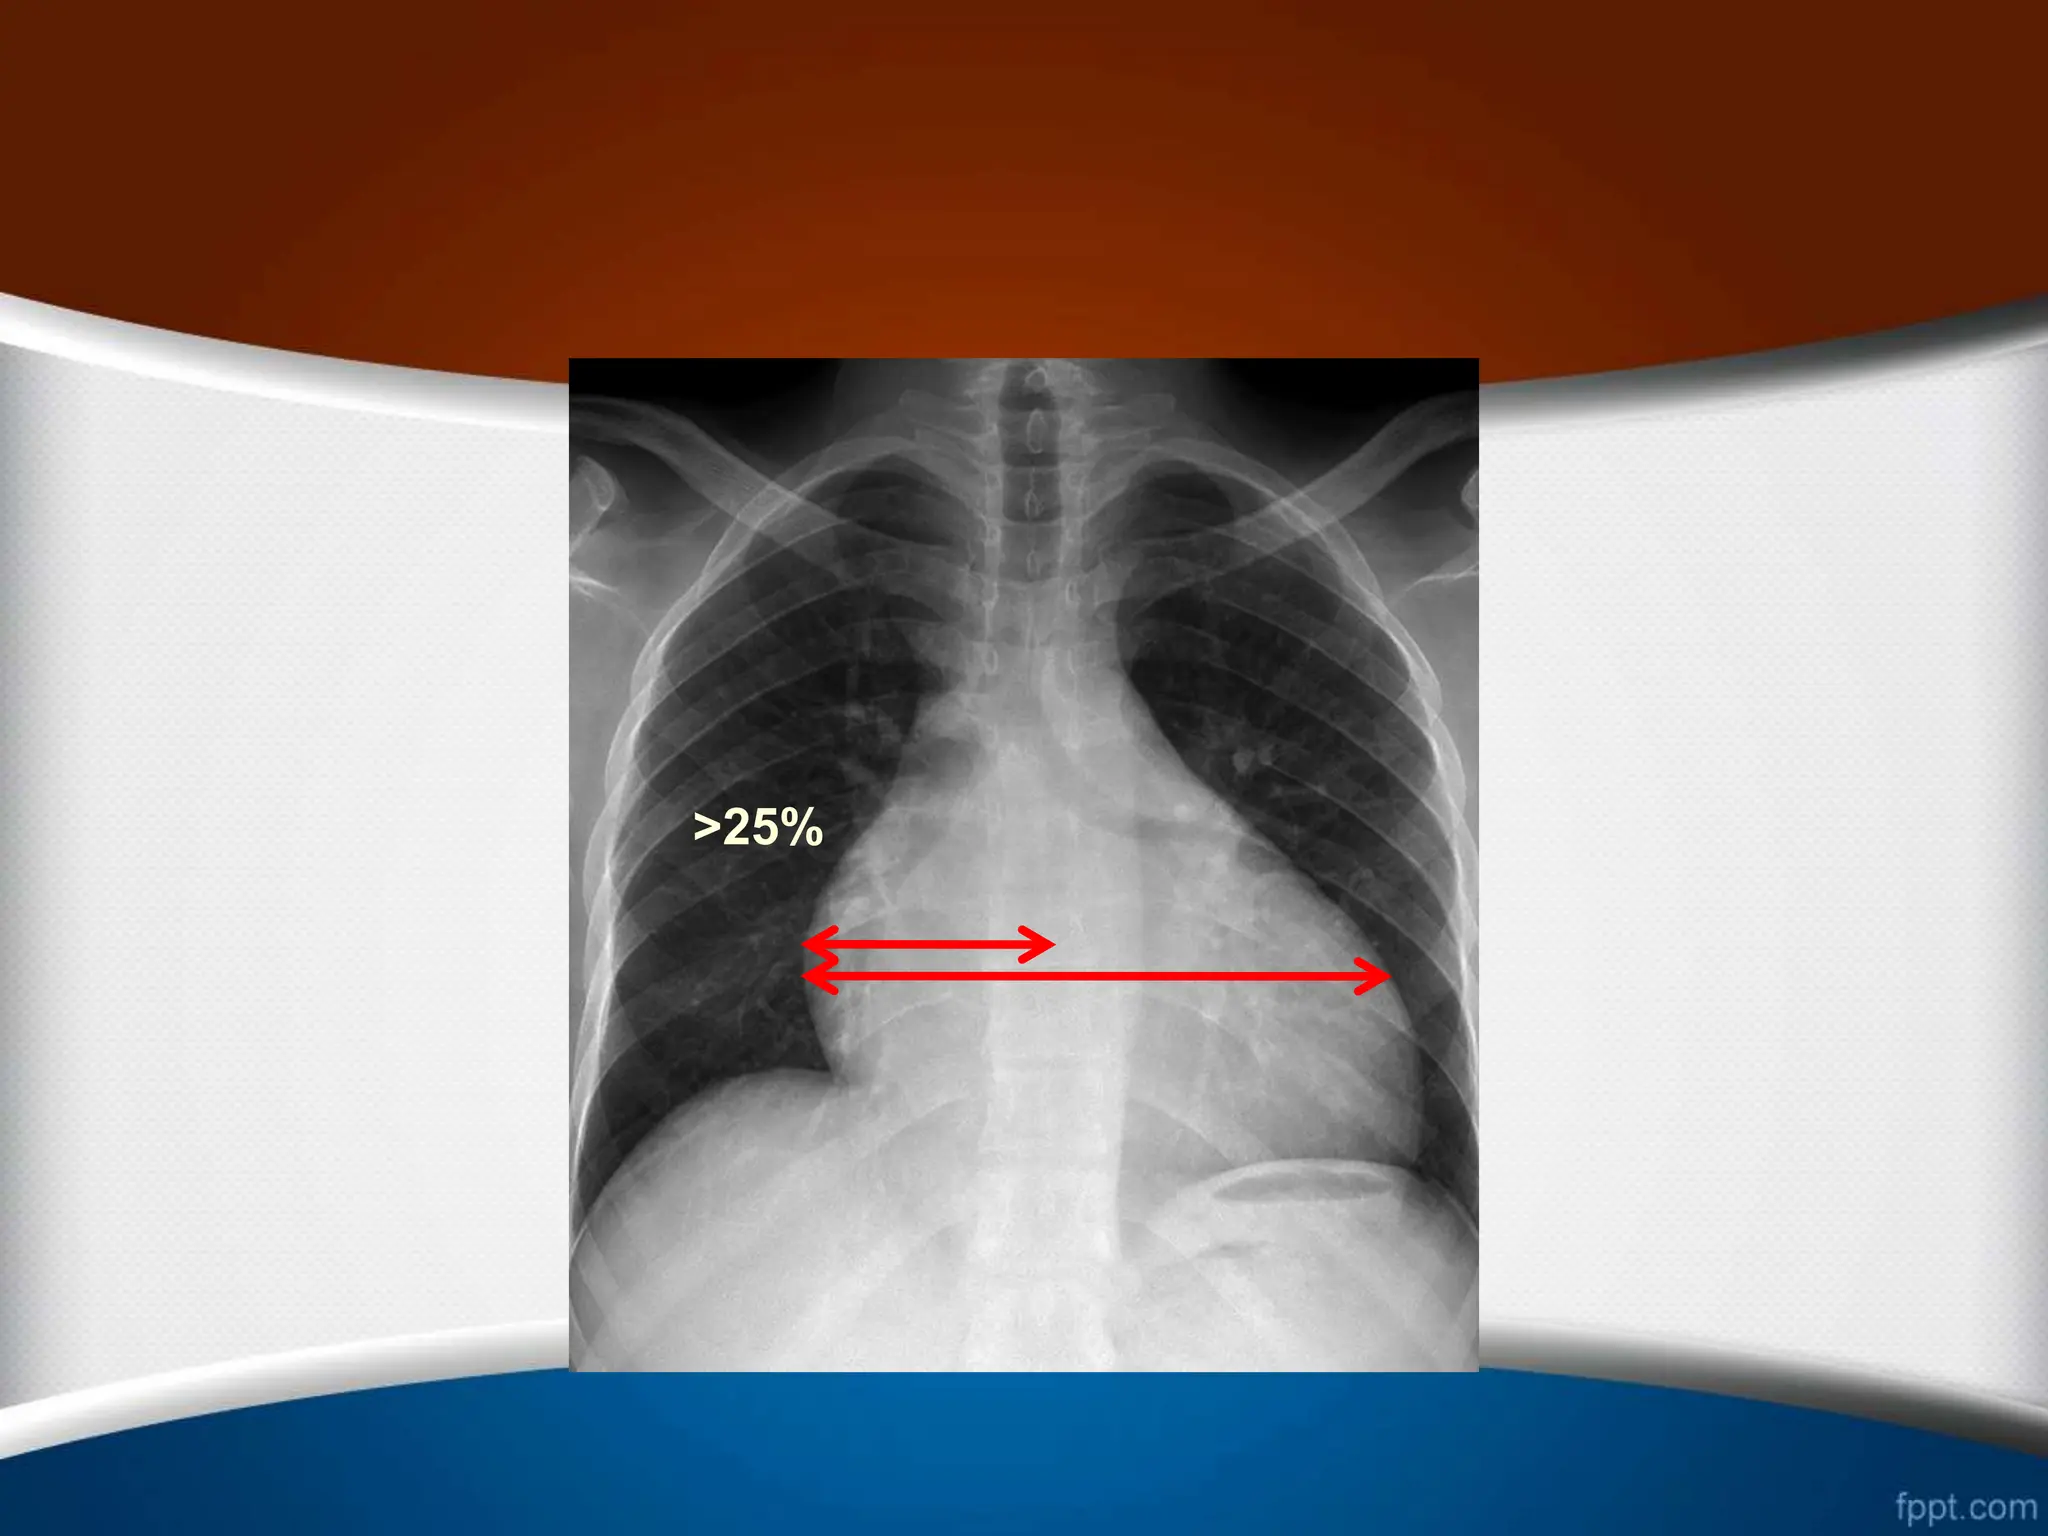

‫راست‬ ‫دهلیز‬ ‫بزرگی‬

.1

‫از‬ ‫بیشتر‬ ‫قلب‬ ‫راست‬ ‫ی‬ ‫کناره‬ ‫افزایش‬

25

%

‫قلب‬ ‫عرضی‬ ‫دیامتر‬

.2

‫راست‬ ‫کاردیوفرنیک‬ ‫ی‬ ‫زاویه‬ ‫شدن‬ ‫باز‬

(

‫منفرجه‬ ‫یا‬ ‫قائمه‬

)

.3

‫از‬ ‫بیشتر‬ ‫وسط‬ ‫خط‬ ‫از‬ ‫راست‬ ‫دهلیز‬ ‫ی‬ ‫حاشیه‬ ‫بین‬ ‫ی‬ ‫فاصله‬

5.5

‫از‬ ‫بیشتر‬ ‫ها‬ ‫مهره‬ ‫ستون‬ ‫راست‬ ‫حاشیه‬ ‫از‬ ‫و‬ ‫متر‬ ‫سانتی‬

2.5

‫متر‬ ‫سانتی‬

.

.4

‫می‬ ‫تشکیل‬ ‫را‬ ‫توراکس‬ ‫همی‬ ‫سوم‬ ‫یک‬ ‫از‬ ‫بیشتر‬ ‫راست‬ ‫دهلیز‬

‫دهد‬

.5

‫راست‬ ‫دهلیز‬ ‫و‬ ‫صعودی‬ ‫آئورت‬ ‫و‬ ‫راست‬ ‫دهلیز‬ ‫بین‬ ‫ی‬ ‫زاویه‬

‫شود‬ ‫می‬ ‫واضح‬

>5.5cm

>2.5cm

>25%

>1/3

‫راست‬ ‫دهلیز‬ ‫بزرگی‬ .1 ‫از‬‫بیشتر‬ ‫قلب‬ ‫راست‬ ‫ی‬ ‫کناره‬ ‫افزایش‬ 25 % ‫قلب‬ ‫عرضی‬ ‫دیامتر‬ .2 ‫راست‬ ‫کاردیوفرنیک‬ ‫ی‬ ‫زاویه‬ ‫شدن‬ ‫باز‬ ( ‫منفرجه‬ ‫یا‬ ‫قائمه‬ ) .3 ‫از‬ ‫بیشتر‬ ‫وسط‬ ‫خط‬ ‫از‬ ‫راست‬ ‫دهلیز‬ ‫ی‬ ‫حاشیه‬ ‫بین‬ ‫ی‬ ‫فاصله‬ 5.5 ‫از‬ ‫بیشتر‬ ‫ها‬ ‫مهره‬ ‫ستون‬ ‫راست‬ ‫حاشیه‬ ‫از‬ ‫و‬ ‫متر‬ ‫سانتی‬ 2.5 ‫متر‬ ‫سانتی‬ . .4 ‫می‬ ‫تشکیل‬ ‫را‬ ‫توراکس‬ ‫همی‬ ‫سوم‬ ‫یک‬ ‫از‬ ‫بیشتر‬ ‫راست‬ ‫دهلیز‬ ‫دهد‬ . .5 ‫راست‬ ‫دهلیز‬ ‫و‬ ‫صعودی‬ ‫آئورت‬ ‫و‬ ‫راست‬ ‫دهلیز‬ ‫بین‬ ‫ی‬ ‫زاویه‬ ‫شود‬ ‫می‬ ‫واضح‬ .